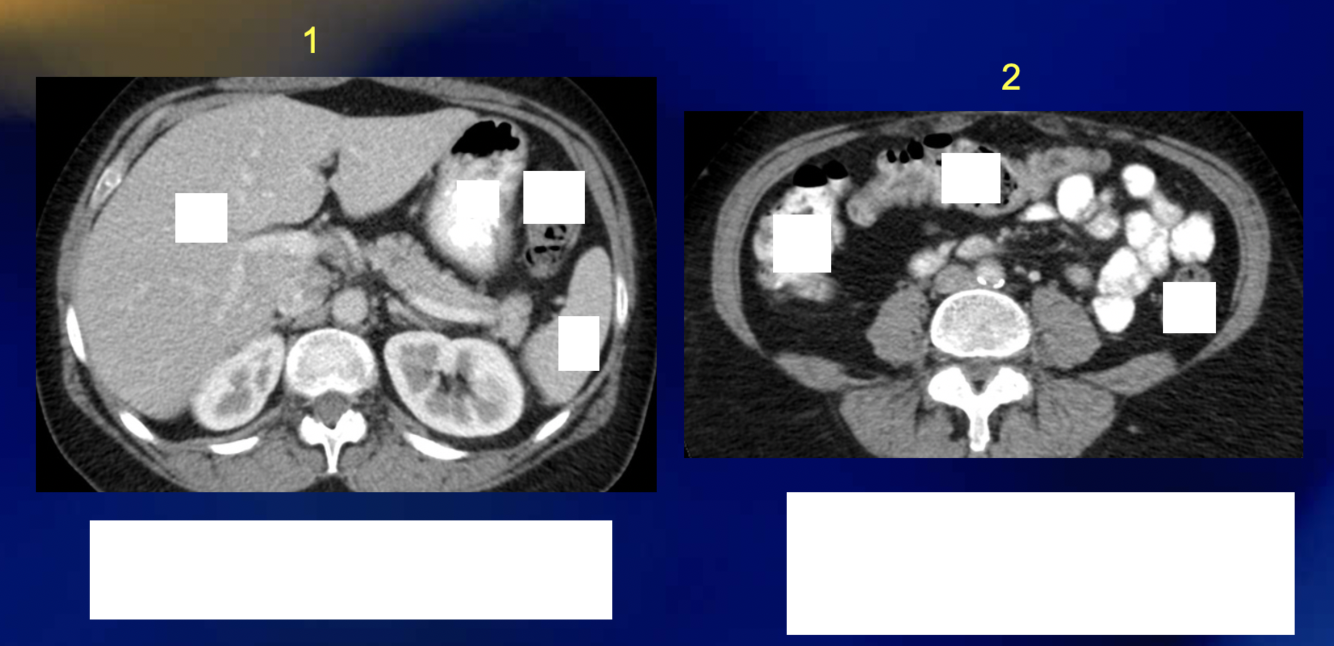

What is seen on the ascending colon?